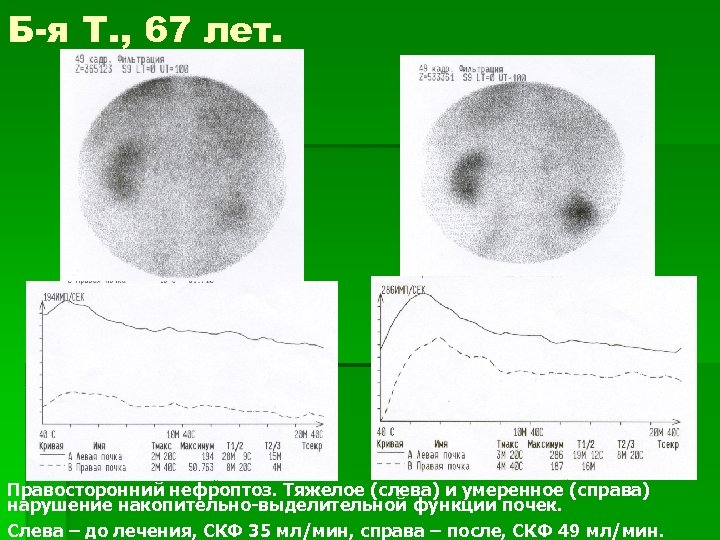

Б-я Т. , 67 лет. Правосторонний нефроптоз. Тяжелое (слева) и умеренное (справа) нарушение накопительно-выделительной функции почек. Слева – до лечения, СКФ 35 мл/мин, справа – после, СКФ 49 мл/мин.